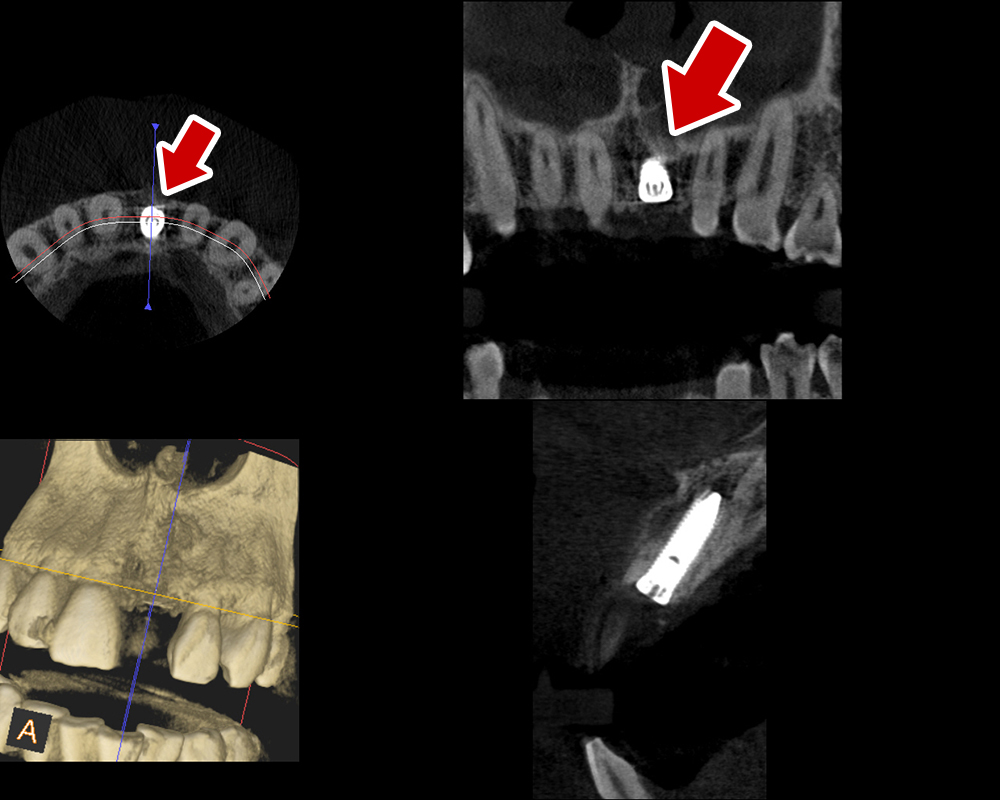

29歳 男性 歯科医療関係者紹介。また、お姉さんが歯科医療関係者。

- 主訴

- 左上1番目の歯が長期にわたり痛く、噛めない。

- 処置内容

1本インプラント埋入+再生療法。抜歯即時埋入、即時荷重法⇒抜歯を行い、

同時にインプラント埋入(即時埋入)、そして同時にインプラントへ仮歯を装着(即時荷重)

歯が無い期間なく、社会生活に支障が出ない

- 治療費用

- 約39万円(税込)

- 治療期間

9か月

手術当日に人工歯(仮歯)まで装着。 (通常待機期間は1年必要です。 (抜歯後6か月+インプラント(根)待機期間6か月+仮歯2か月))

- リスク

- 上部構造物、仮歯の破折、術後の腫れ(3日)、人工歯根脱落リスクがあります

- その他

- 学術雑誌、海外公演(アメリカ、ヨーロッパ)に多く紹介されたケース